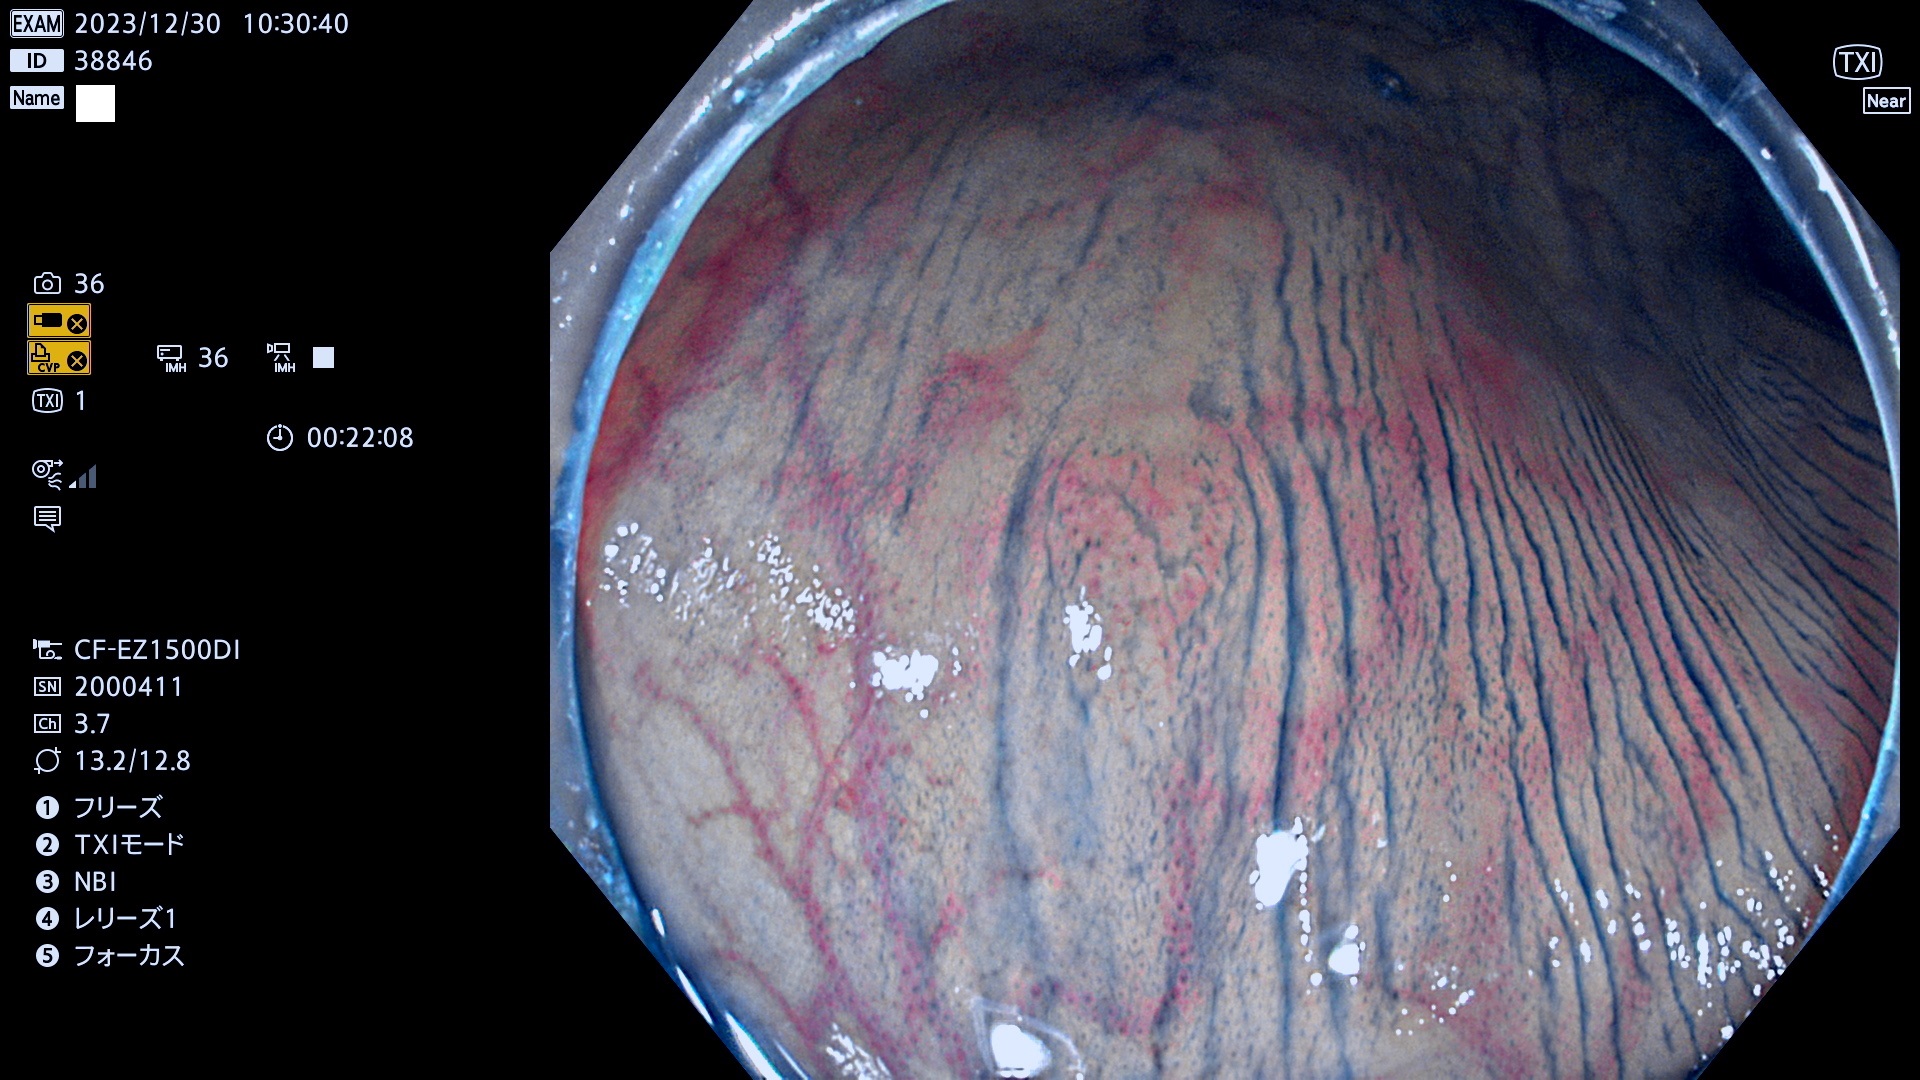

表面型腺腫(Flat Adenoma)の中で、完全に平坦な物をUb、陥凹している物をUcと呼びます。平坦隆起型(Ua)よりも、発見が難しく危険な病変です。

毎週の検査(木・金・土・日)に発見されたUb、Uc型・腺腫を、その週の日曜の夜にUPし1週間、提示します。

抽出の対象期間 2023年12月28日(木)〜12月31(日)の4日間(48件の検査)7件